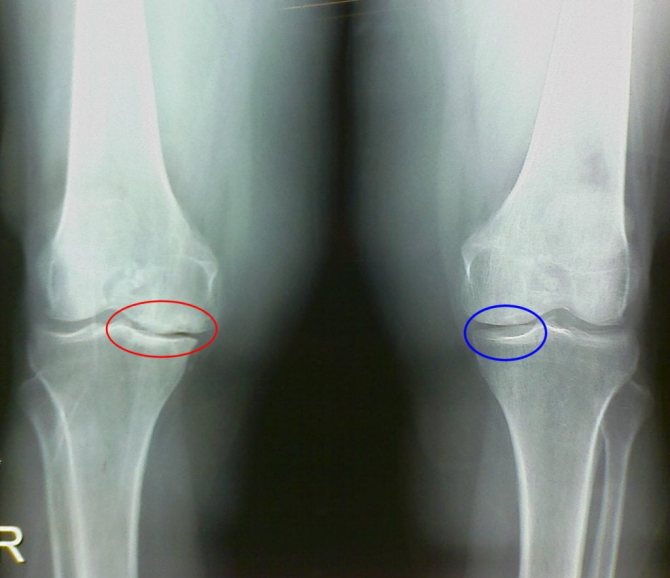

Для изучения структурно-модифицирующего действия глюкозамина и хондроитина проводились длительные двойные слепые плацебоконтролируемые исследования. В испытаниях принимали участия добровольцы с остеоартрозом коленного сустава — тяжелой дегенеративно-дистрофической патологией. А основным оценочным критерием терапевтической эффективности хондропротекторов являлось изменение размеров суставной щели. Пациенты на протяжении двух лет принимали хондроитин в дозе 0,8 г в сутки. В результате было обнаружено стабилизирующее влияние хондропротекторов на размеры суставной щели.